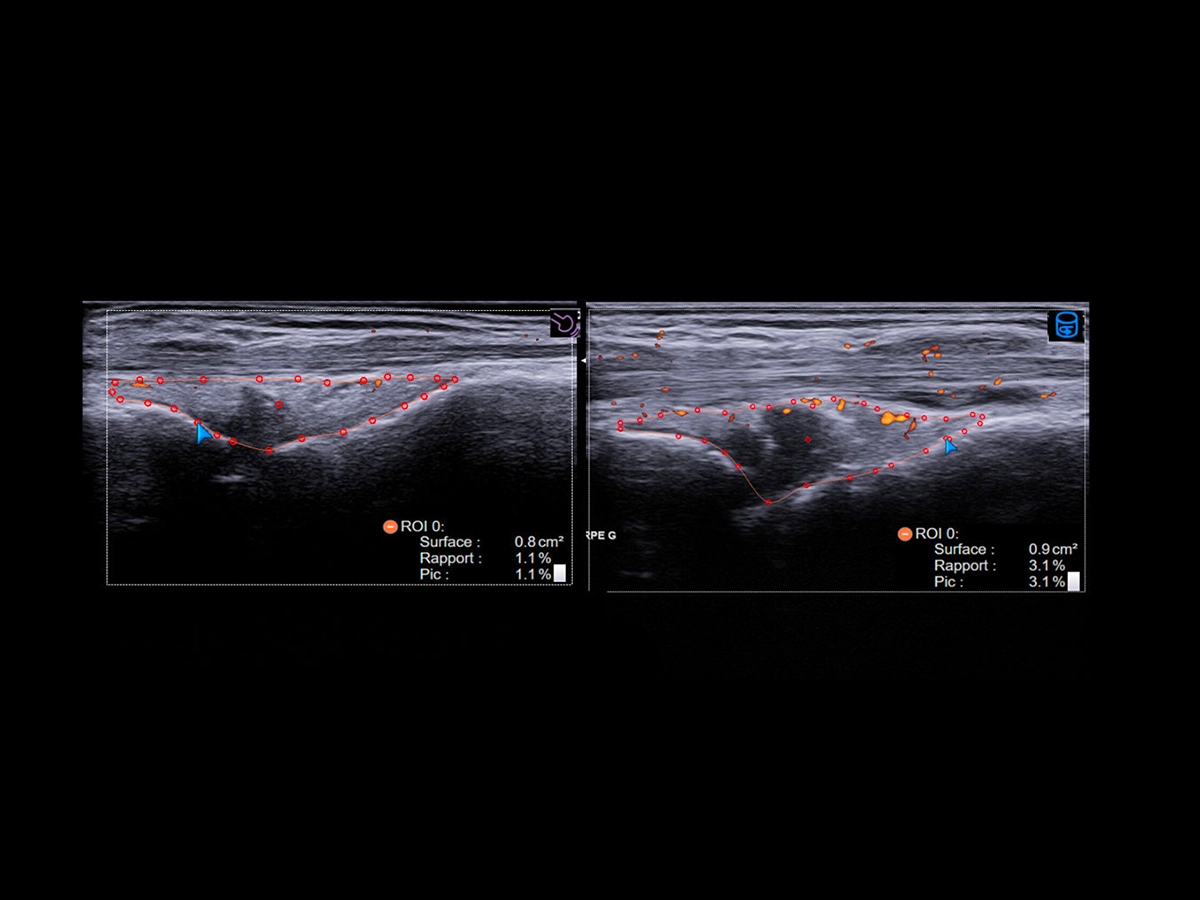

Follow-up in rheumatology plays a pivotal role in the effective management of rheumatic diseases by monitoring disease progression and piloting the therapy. The Follow Up & Multimodality tool developed by Esaote allows a comparison between real-time US and a second ultrasound image or a second modality image.

This technology can be used together with the QPack one, as it is crucial for rheumatologists to assess and quantify how the level of flows change over time in the same target areas.